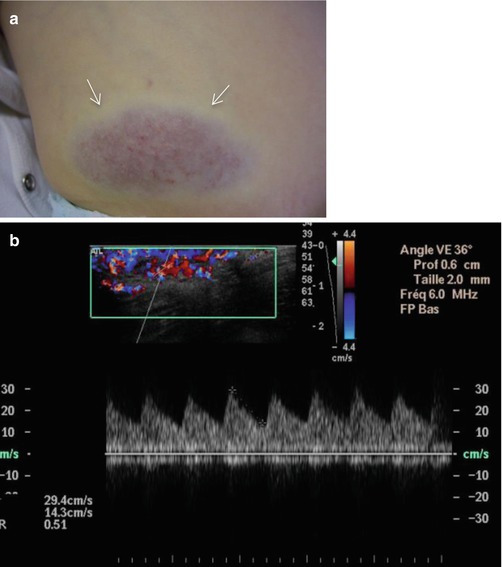

- Noninvoluting congenital hemangiomas (NICH), which demonstrate growth proportional to that of the child without regression (Fig. 16.4).Fig. 16.4

Congential hemangioma in a 3-year-old boy. (a) Clinical photograph. (b) Axial color Doppler image with spectral display obtained in tumor center. (a) Non-involuting congenital hemangioma (NICH) is seen as an overlying bluish discoloration with clear peripheral halo (arrow). The lesion has been present since birth, growing proportionally to the patient’s growth. (b) Color Doppler image shows the marked increased vascularity inside the lesion with low-resistance arteries. The imaging features are indistinguishable from those of infantile hemangioma